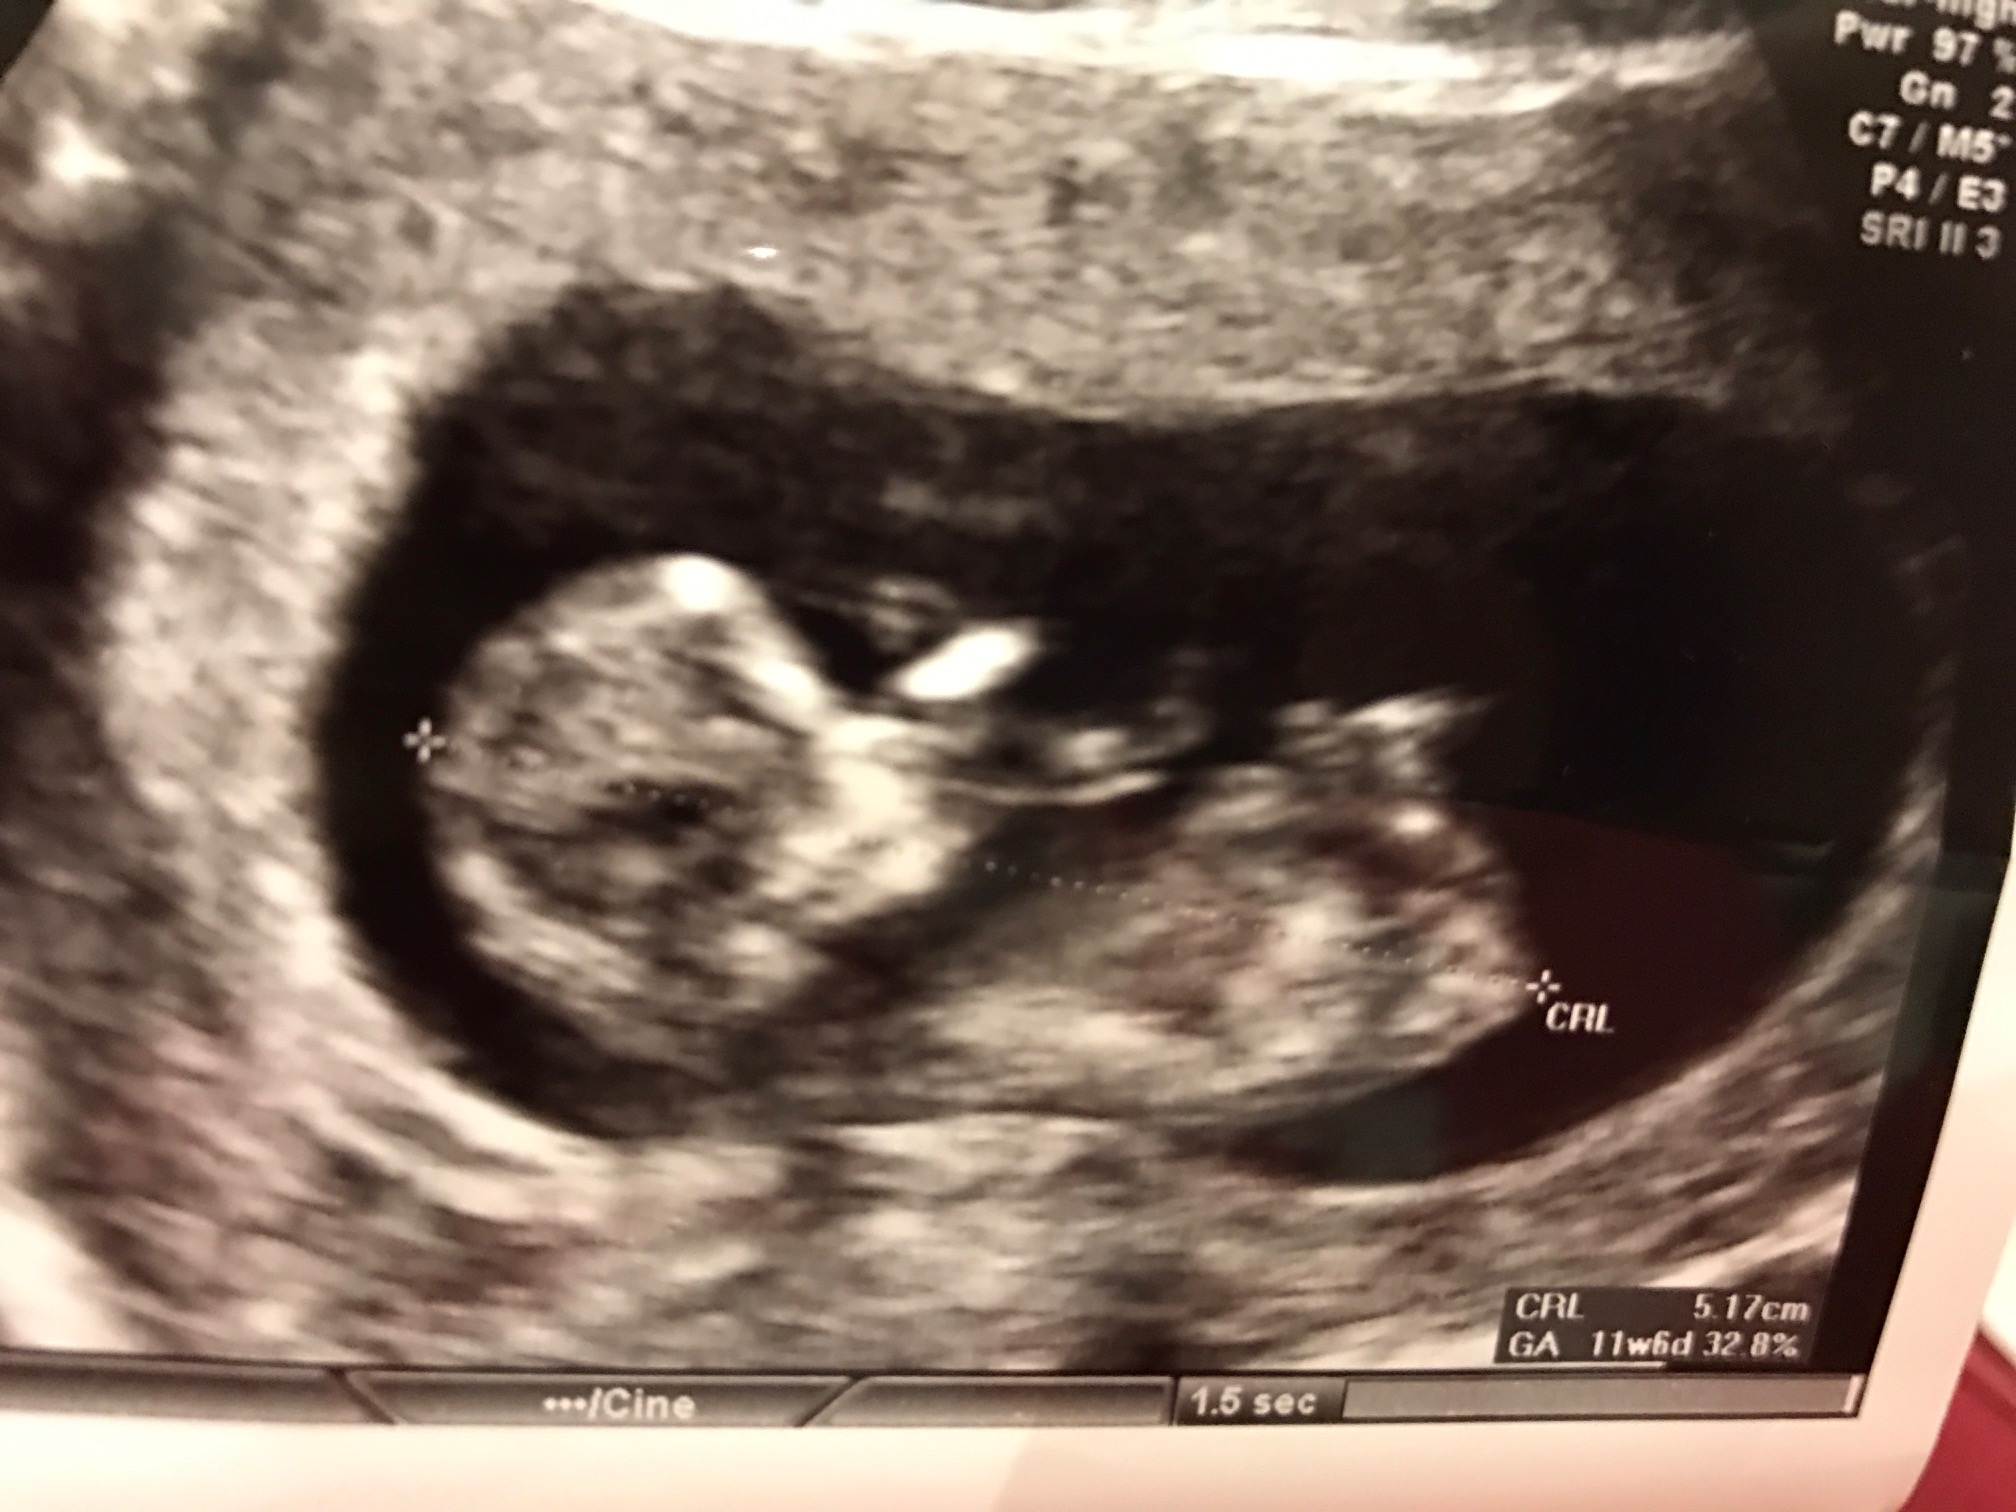

Boy or girl?

Any guess by skull or nub theory?